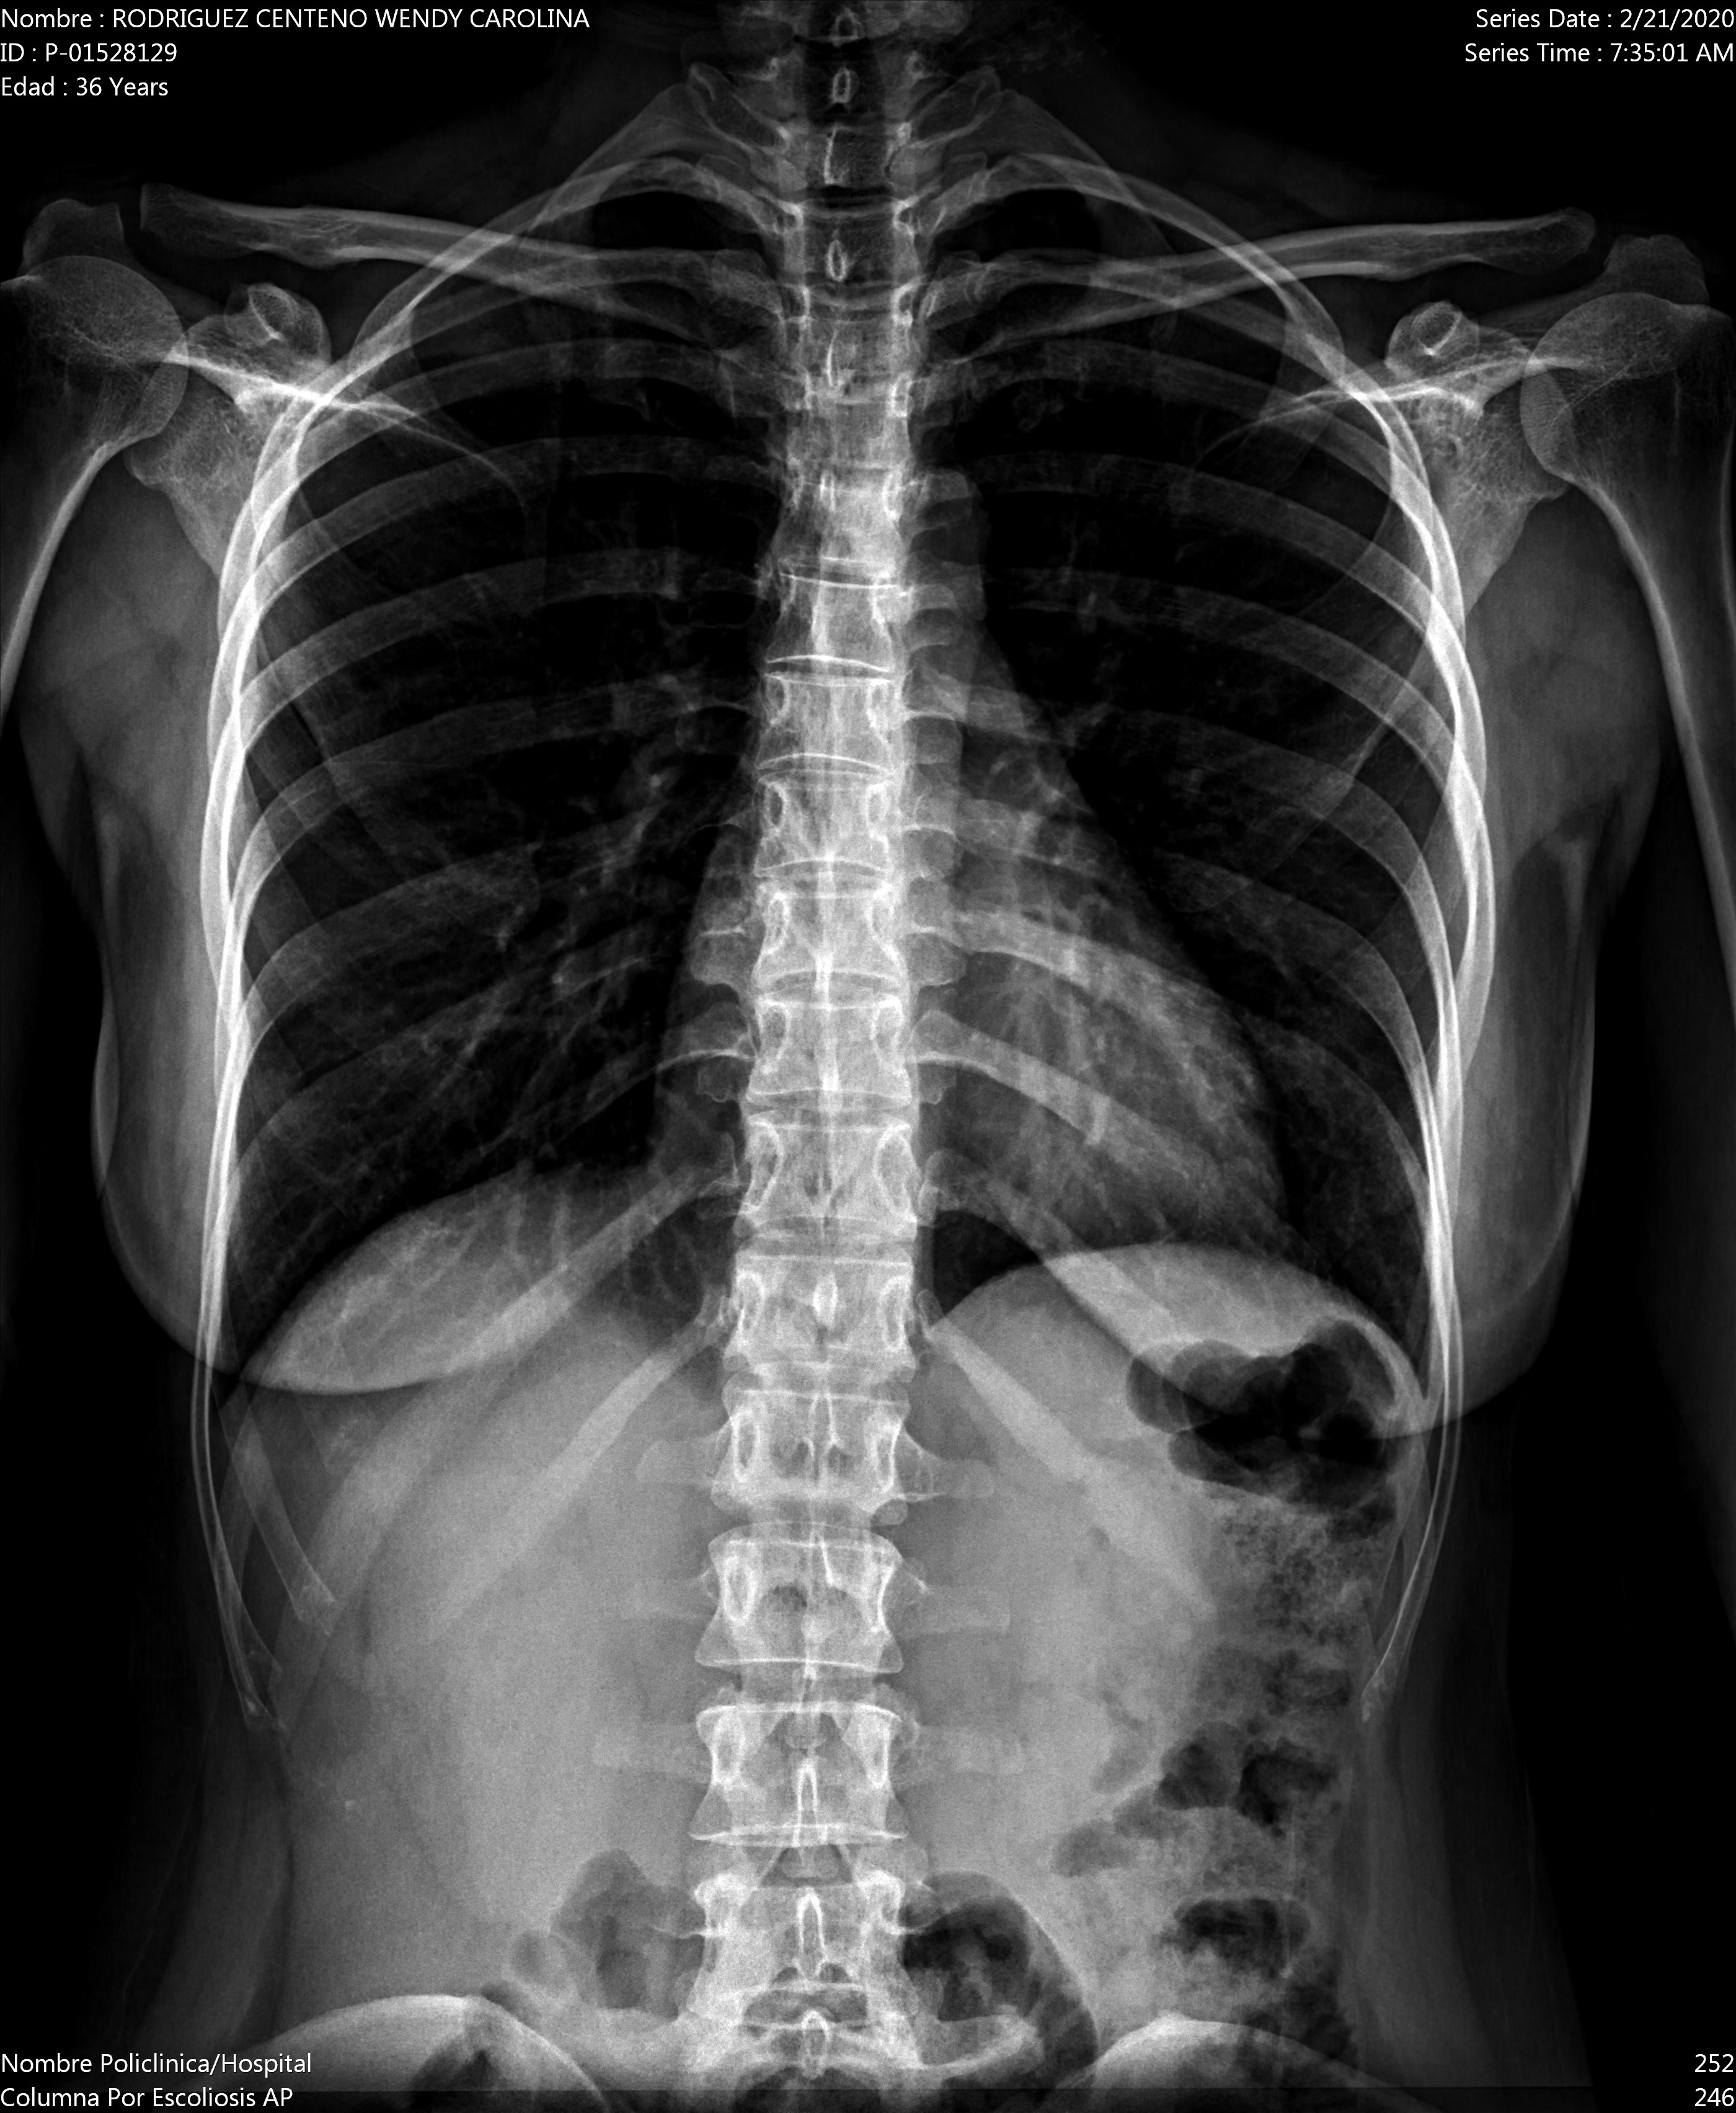

Ho un forte dolore al bacino. Il dolore è più acuto quando devo alzarmi da una sedia e non posso camminare se non lentamente per il forte dolore.

Allego i raggi x appena fatti.

Buongiorno signora. Alle rx non si vede nulla di particolare. Dovrebbe sentire uno specialista quando questa crisi sanitaria sarà risolta. Cordiali saluti